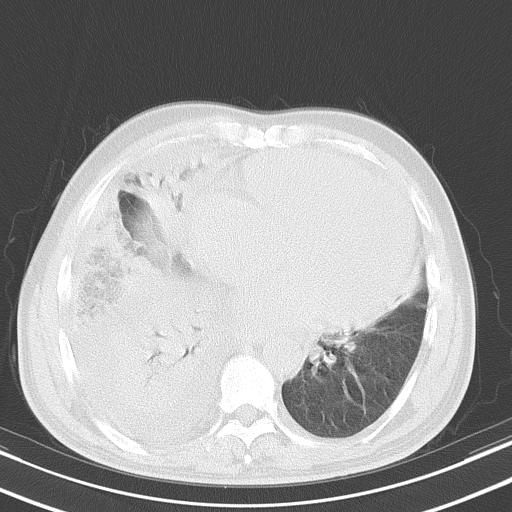

以下是引用zjzjr在2010-3-21 17:39:00的发言:[br]右下中心型肺癌并阻塞性肺炎/不张,纵膈淋巴结肿大,右侧大量胸腔积液,左侧少量胸腔积液

以下是引用zxl51642在2010-3-21 17:06:00的发言:[br]右下中心型肺癌并阻塞性肺炎/不张,纵膈淋巴结肿大,右侧大量胸腔积液,左侧少量胸腔积液,少量腹水。建议纤维支气管镜进一步检查。